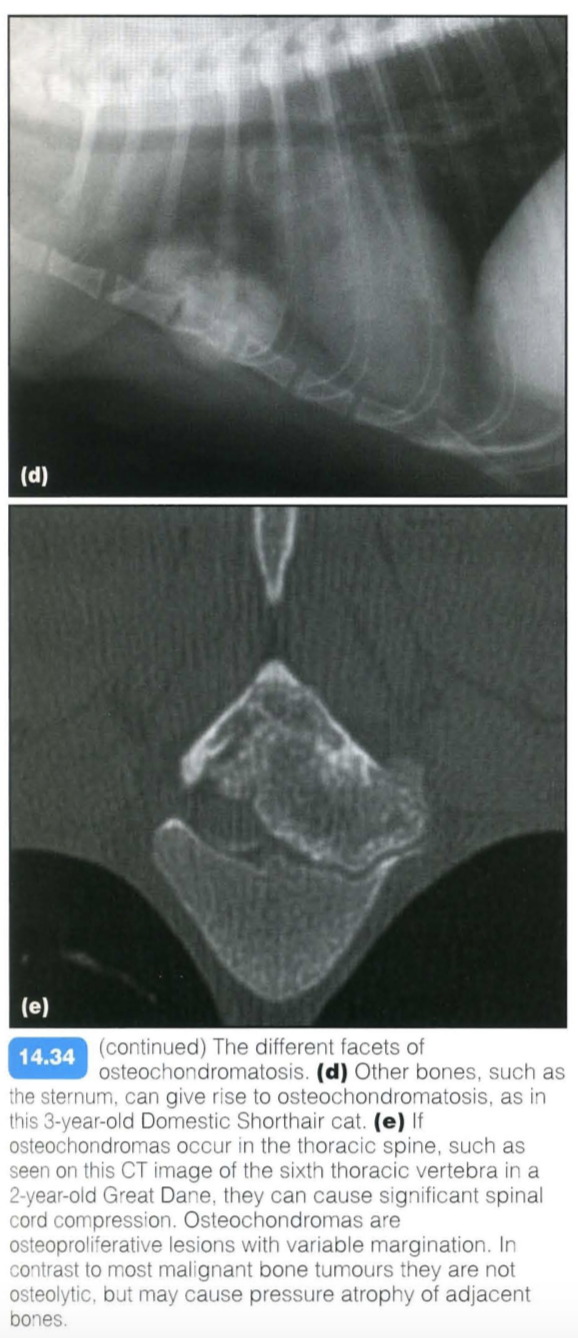

This is a skeletal dysplasia (a form of hamartoma) associated with expansile bony lesions, which usually arises from the osteochondral junction of bones. The lesion usually stops growing at the time of skeletal maturity.

In rare cases malignant transformation may occur. Commonly affected areas are the costochondral rib junctions; less frequently, the metaphyses of the long bones and vertebrae may be involved. Small rib lesions are common in dogs, but rare in cats. The condition can affect multiple sites simultaneously (multiple cartilaginous exostoses).

Clinical signs are usually related to lameness or paresis/paralysis in the case of spinal cord compression.

Other imaging techniques: CT or magnetic resonance imaging (MRI) may be used to assess spinal cord compression of vertebral osteochondroma.